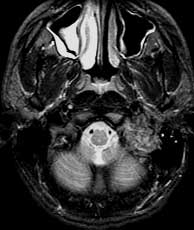

T2 SE axials

Findings: Mostly bright signal mass in the left medial skull base which abuts the basiocciput (basi) and invades the left external auditory canal (eac). The mass has several linear and curvilinear foci of decreased signal within.